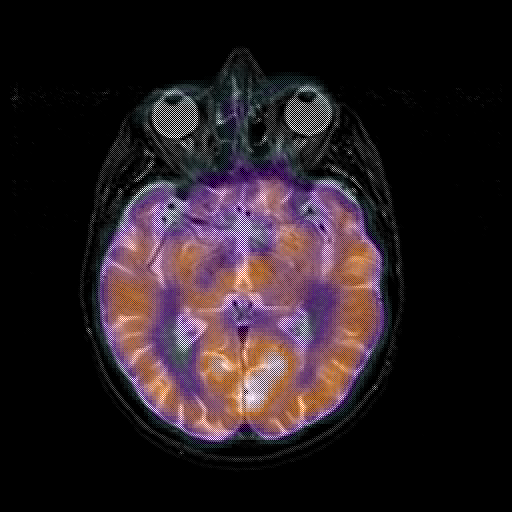

overlay 1: Slice 25

Slice 25

MRCBFCBF with

T1PDT2T1PDT2